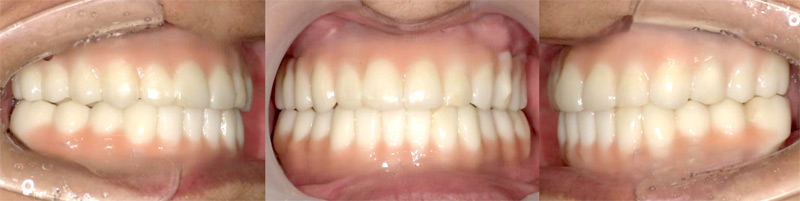

施行名 : 審美歯科(虫歯などをインプラント体によって改善する施術)

副作用やリスク : 麻酔で腫れやむくみを生じる場合があります。

また、劣化や口内の手入れを怠ることにより脱落する場合があります。

施術の価格:8万〜90万(税抜き)

※個人差があり、効果を保障するものではありません